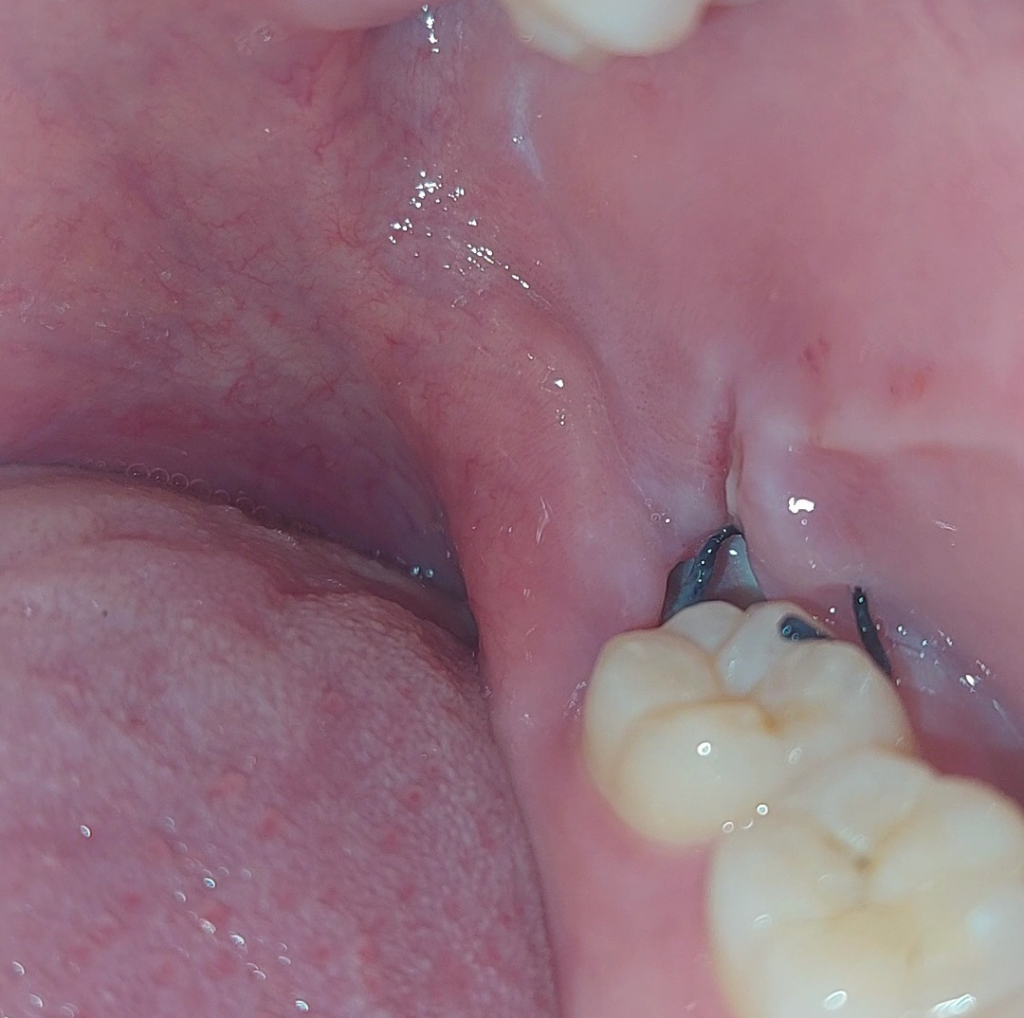

사랑니 발치부위에 웬 빵꾸가났어요. 깊이도 꽤 깊어요.

아래쪽 사랑니를 발치하고 5일차입니다

지금보니까 깊이도 꽤 깊고 안쪽은 회색을띄고있습니다.

• 3번 째 사진

사진상으론 크게 치유부전이 일어나거나 감염이 일어난 것처럼 보이진 않습니다.

(부분)매복 사랑니를 빼기 위해 절개를 했고 봉합까지 되어 있는 상태인 것 같은데 매복 사랑니의 경우 빼는 과정에서 뼈를 치는 등 다소간 마취가 풀린 후 통증을 유발할 수 있는 요소가 있긴 합니다.

발치 후 2~3일, 최대 일주일 정도까지도 통증이 있을 수 있으나 진통제를 드시면 증상 완화에는 도움이 됩니다.

발치 부위 구멍은 잇몸이 초기 치유가 일어나면서 자연스럽게 닫힙니다.

초기 치유는 1~2주 정도 걸리고 혈병의 경우 발치 후 24시간 이내에 형성되어 1~2일차에 자연스럽게 상피조직으로 바뀌게 되며 현재는 치유과정 중에 있는 것으로 보입니다